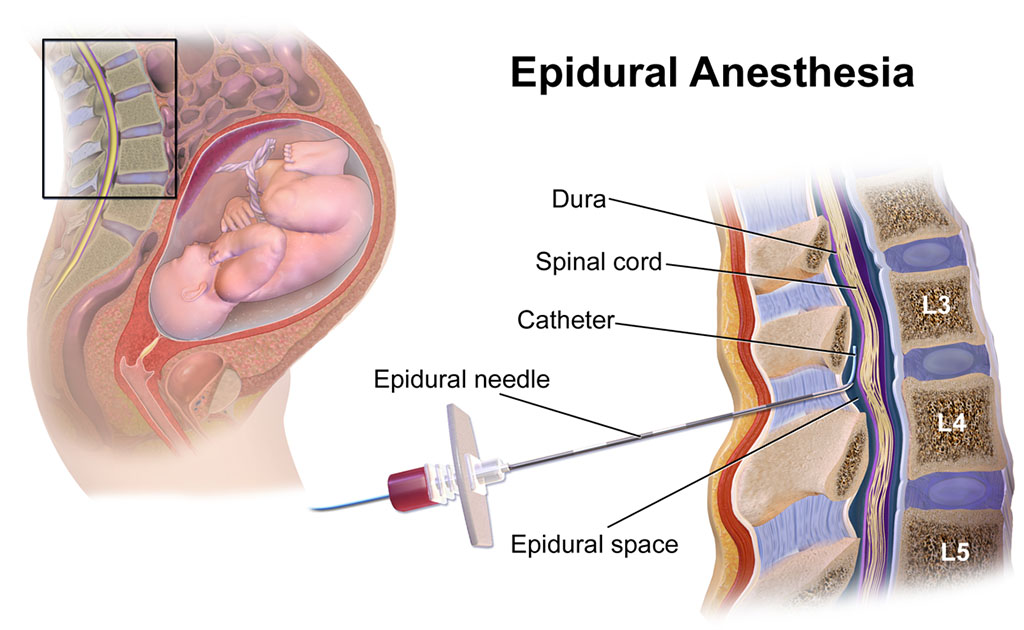

ব্যথামুক্ত নরমাল ডেলিভারি | এই প্রক্রিয়ার সুবিধাগুলো কী কী?

0 SHARES Share Tweet প্রেগনেন্ট মায়েদের কাছ থেকে ব্যথামুক্ত নরমাল ডেলিভারি সম্পর্কিত নানা ধরনের প্রশ্ন শোনা যায়। এই প্রক...